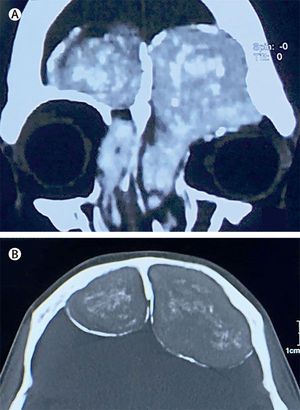

Frontal nasal lesion A 27-year-old man had a 4-month history of bilateral frontal headache, irritability, frontal lobe signs, bilateral proptosis, and nasal obstruction. Craniotomy revealed intracranial extension of a grey-coloured, foul smelling, soft tissue mass extending from the nasal sinuses. 1) Allergic rhinocerebral aspergillosis 2) Angiofibroma 3) Nasopharyngeal carcinoma with skull base extension 4) Fibrous dysplasia